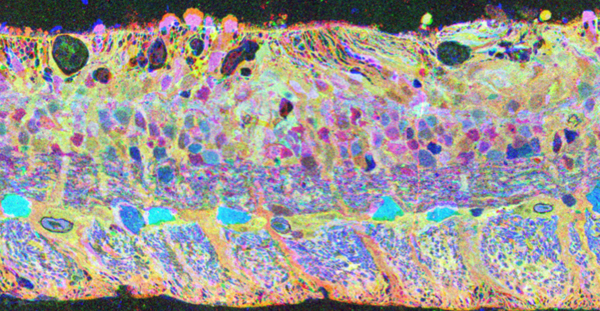

Detection of neuron membranes in electron microscopy images using a serial neural network architecture

The Viking viewer for connectomics: scalable multi-user annotation and summarization of large volume data sets